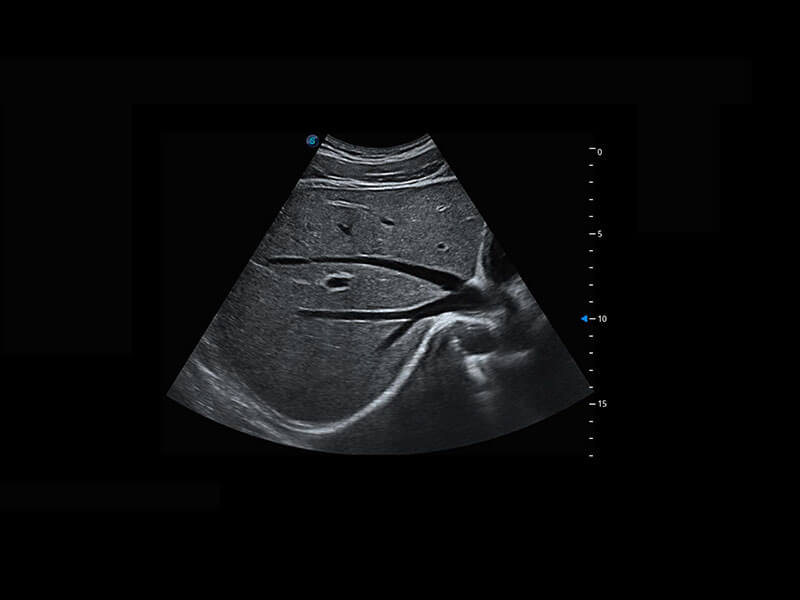

腔内妇科-宫腔分离

腔内妇科-卵巢

腔内三维-宫内节育器

P60优异的图像质量搭载专科探头,在妇科基础疾病的诊断、卵泡生长的监测、输卵管通畅情况的判别等方面为您提供生殖应用方案。